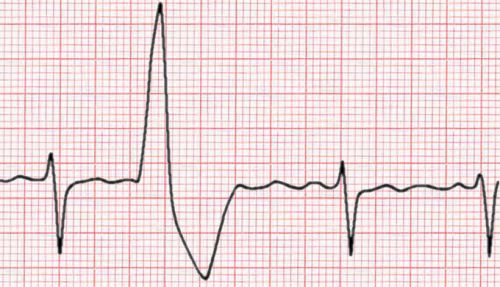

3. ES ventriculare

- Sunt

batai ventriculare premature, initiate de un focar ectopic situat la

nivelul miocardului ventricular

- Complexele

QRS sunt largite > 0,13 sec, deformate, neregulate

- Lipseste

unda P

- Intervalul

RR` < intervalul RR normal, al ritmului de baza

- ESV

sunt urmate de pauza compensatorie

- R`R +

R`R = 2RR

nu depolarizeaza retrograde atriile